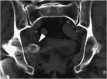

Various complications occur during total hip arthroplasty (THA). It is common to implement trial treatments of various implants during THA. Here we report on 2 cases in which the trial femoral head fell into the pelvis and migrated during THA. The trial head was not retrieved but left inside in one case, while the other presented the opportunity for a possible retrieval. It is important to recognize the existence of such rare complications.